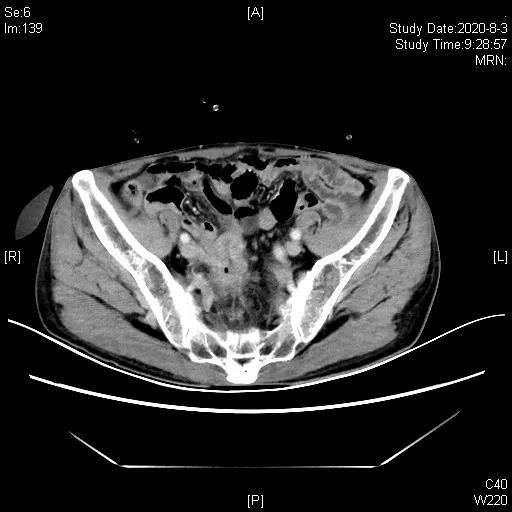

三线治疗:2020-05-25“培美曲塞700mg+阿帕替尼0.25gQD”治疗,期间腹腔造瘘口间断有极少量出血,鉴于患者停用抗生素已3月,于2020-06-19、07-11行“PD-1抑制剂(信迪利单抗)200mg+阿帕替尼0.25qd+培美曲塞0.7”治疗2周期,造瘘口出血停止,2020-08-03CT评估近期疗效:部分缓解(PR)。

三线治疗3周期后,影像学评估缩小,PR